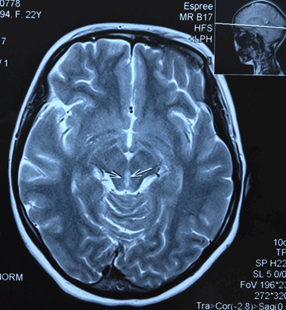

Пациентка направляется на МРТ головного мозга без контрастирования с подозрением на синдром Вернике и образование ГМ (рис.).

МРТ головного мозга без контрастирования пациентки Ч. Поражение вещества мозга по ходу паравентрикулярных отделов варолиева моста, водопровода и медиальных отделов таламуса

Результаты МРТ головного мозга пациентки: «Топография срединных структур мозга не изменена. Обращает внимание поражение вещества мозга по ходу паравентрикулярных отделов варолиева моста, водопровода и медиальных отделов таламуса. В белом веществе лобно-теменных долей с обеих сторон определяются очаги лейкопатии. Мозолистое тело, гипоталамо-гипофизарная область, продолговатый мозг и мозжечок без особенностей. Область мостомозжечковых углов без патологических изменений. Желудочковая система мозга не расширена и не деформирована. Конвекситальные субарахноидальные пространства и базальные цистерны мозга не расширены. Соотношения в краниовертебральном переходе не нарушены. На скрининговой МР-ангиографии Виллизиева круга признаков артериовенозной мальформации и аневризм сосудов головного мозга не выявлены. Заключение: МР-признаки энцефалопатии Вернике. Очаги лейкопатии в белом веществе лобно-теменных долей с обеих сторон, вероятно, как проявление резидуальной энцефалопатии».